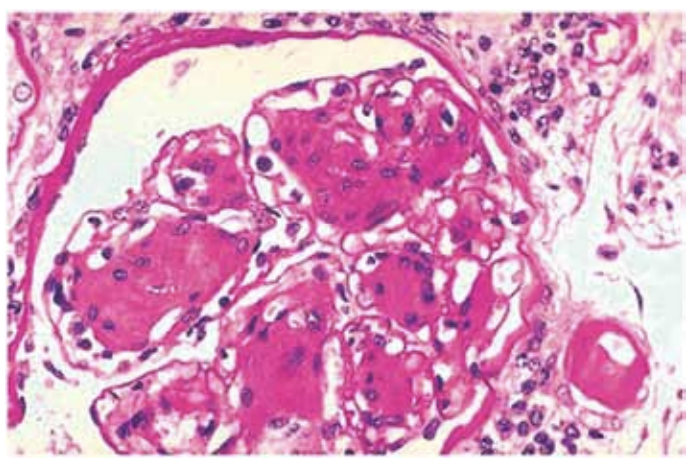

Mulher de 18 anos, com diagnóstico de lúpus eritematoso sistêmico (LES), realizou biópsia renal.

Microscopia ótica: 24 glomérulos, 18 dos quais comprometidos conforme imagem a seguir:

A classificação da nefrite lúpica é: